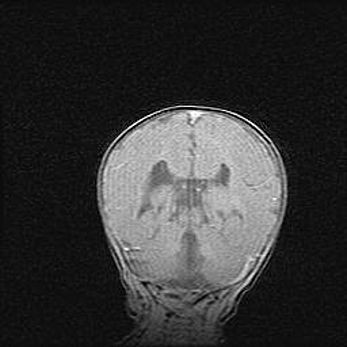

Церебральная ишемия II.

Возраст: 5 дней

Вес: 3400 г

Пол: женский

Окружность головы: 35 см

Срок гестации: 39 недель

Церебральная ишемия – это заболевание, характеризующееся недостаточностью (гипоксией) либо полным прекращением (аноксией) снабжения мозга кислородом по причине закупорки одного или нескольких сосудов. Это приводит к  что метаболическим расстройствам различной степени тяжести в тканях головного мозга, развитию коагуляционных некрозов и гибели нейронов.